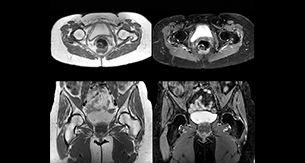

“For bone assessment near joints, mDIXON TSE provides the visualization and multiple contrasts to describe abnormalities within a limited number of acquisitions. Bone marrow signal abnormalities are common MRI findings that can represent various underlying causes, from normal variance to malignancy. So, it is important for us to notice and characterize these findings. With different contrasts, both with and without fat signal as mDIXON TSE efficiently provides, we can make a confident diagnosis.” “Other examples in bone are the signal description of a necrotic fragment in osteonecrosis, the signal description of tumoral matrix that has different components (necrosis, hemorrhage, cartilage, bone formation). These are all possible thanks to in-phase and water images from a single mDIXON acquisition.”

“In peripheral joints, mDIXON TSE imaging aids in diagnosing injuries in ligaments or tendons, for imaging degenerative and inflammatory pathologies such as osteoarthritis and rheumatologic disorders and for oncological exploration.” “For tendon and ligament assessment around knee, ankle, hip and elbow, mDIXON TSE contributes to diagnostic confidence thanks to having images both with and without fat suppression – and without time penalty. This is possible because 2-point mDIXON is faster than the common 3-point Dixon method. It can also increase efficiency as it helps avoid having to add scans during the exam.” “mDIXON TSE sequences allow simultaneous characterization of morphological changes from the in-phase T2-weighted images and visualization of edematous changes, thanks to the water T2-weighted images from the same acquisition. Anatomical and morphological considerations could be a partial or complete ligament tear, a bony avulsion or hematoma.” “For soft tissue assessment mDIXON brings similar benefits. For example in one T2-weighted mDIXON TSE acquisition, having the multiple contrasts helps us assess abnormalities in peripheral nerves fascicles, which may be due to anatomical or inflammatory changes..” “In peripheral joints, we get good image quality in difficult areas with mDIXON TSE. Fat suppressed images appear homogeneous over the entire image, even with large coverage at 3.0T – for instance in scapular or hip girdles – or in the bearing areas or around metal prostheses*, where fat suppression is often deficient with STIR or spectral fat suppression, causing diagnostic difficulties. If a diagnostic image is right the first time, we don’t need to repeat or add a sequence.” “mDIXON TSE sequences allow simultaneous characterization of morphological changes from the in-phase T2-weighted images and visualization of edematous changes, thanks to the water T2-weighted images from the same acquisition. Anatomical and morphological considerations could be a partial or complete ligament tear, a bony avulsion or hematoma.” “For soft tissue assessment mDIXON brings similar benefits. For example in one T2-weighted mDIXON TSE acquisition, having the multiple contrasts helps us assess abnormalities in peripheral nerves fascicles, which may be due to anatomical or inflammatory changes..”